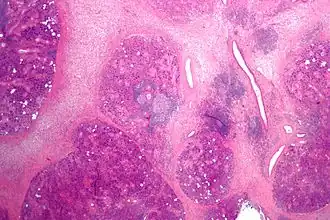

Патоморфология

Расширение протока с задержкой слюноотделения, гроздевидная атрофия или утолщённая и отёчная слизистая оболочка, гнойный или серозно-гнойный экссудат внутри протока, замещение железистой ткани фиброзной, инфильтрация лейкоцитами.